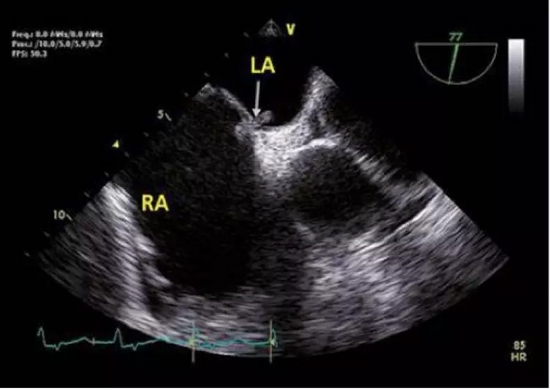

列位看官,你们肯定忽视了一种心脏疾病所致的偏头痛:卵圆孔未闭。

卵圆孔其实是心房原发隔与继发隔之间的一个缝隙。由于这个解剖结构的存在,当情绪激动等其他原因导致胸腔内压力过高时,可能会导致心房之间出现右向左的分流。因静脉血中化学物质如 5-羟色胺等血管活性物质较多,在分流后会导致脑血管扩张出现偏头痛。

所以在临床中会有一些不明原因偏头痛的患者,能够卵圆孔未闭封堵中获益。

卵圆孔未闭,一般是左向右分流,在右心压力升高时,可出现右向左分流 卵圆孔未闭,一般是左向右分流,在右心压力升高时,可出现右向左分流